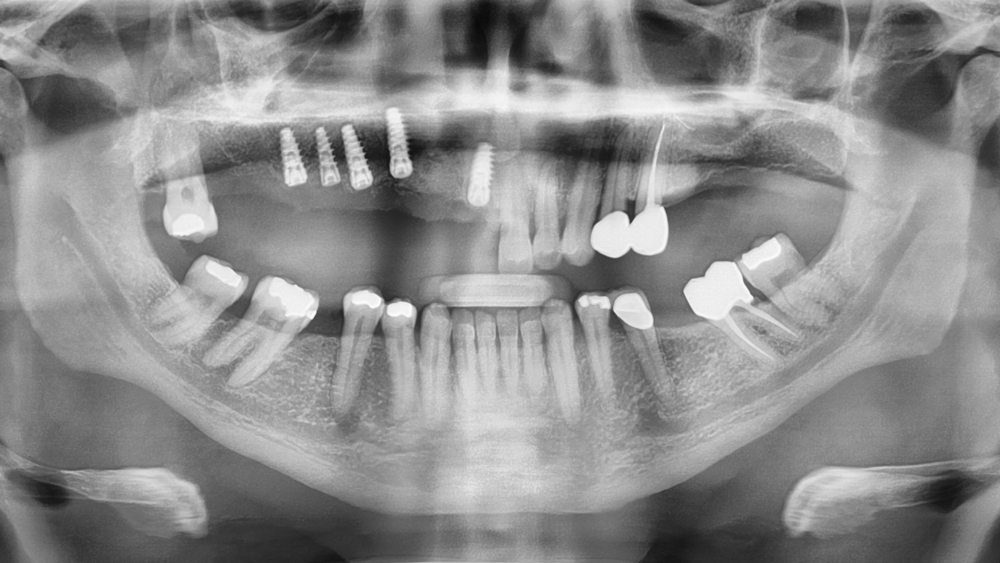

The chief complaint from my patient, Weldon, was missing teeth and gaps between his teeth. The preoperative evaluation showed periodontally involved and non-restorable maxillary right teeth #2–8 and significant periodontal bone loss, which would need to be addressed. The periodontal condition was stable in the patient’s left maxilla, and he was satisfied with the existing esthetics in that quadrant.

The Hahn™ Tapered Implant (Glidewell Direct; Irvine, Calif.) was ideal for this case because it has a pronounced thread design, a machined collar for soft-tissue maintenance, and a prosthetic connection that facilitates platform switching, which serves to preserve bone and gingival tissue around the implant-abutment interface.

Bone Loss

There was significant bone loss on the right side of the maxilla, from the existing non-restorable central incisor back to the second molar. With this bone loss and mobility of the teeth, there was vertical and horizontal deficiency of the available bone. Options considered included an autogenous block graft to attempt to increase bone height and width. The second option was to work with the available bone, extract the non-restorable teeth on the right side of the maxillary arch, immediately place implants, and create esthetics with a longer prosthesis that includes pink-colored gingival areas. A BruxZir Solid Zirconia implant bridge was the optimal long-term solution because the entire prosthesis, including the gingival areas, is milled from a single block of high-strength solid zirconia, affording unmatched durability for this type of restoration. Although Weldon did not have a high smile line, he was attracted to a prosthetic design that included gingival areas to restore esthetics where tissue loss had occurred.

After removing the untreatable teeth, I placed five Hahn Tapered Implants into the extraction sockets, grafted the area with Newport Biologics™ Mineralized Cortico/Cancellous Allograft Blend (Glidewell Direct) mixed with harvested autograft from the osteotomy sites, and used a Newport Biologics Resorbable Collagen Membrane 3-4 (Glidewell Direct) as a barrier against epithelial downgrowth during the healing and remodeling phase.

RESTORING THE CASE

Following integration of the implants for approximately four months, a final impression was made using Hahn Open-Tray Impression Copings (Glidewell Direct). The laboratory created a master cast and fabricated Inclusive® Titanium Custom Abutments for a cementable, implant-supported prosthesis. A screw-retained prosthesis was considered for this case, but because of the angulation of the seated implant fixtures, access holes would have exited through the facial aspect of the final prosthesis. Note that the patient is able to maintain the health of the tissue in the area of the restoration with a water pick, and the BruxZir Solid Zirconia material resists bacterial adhesion.